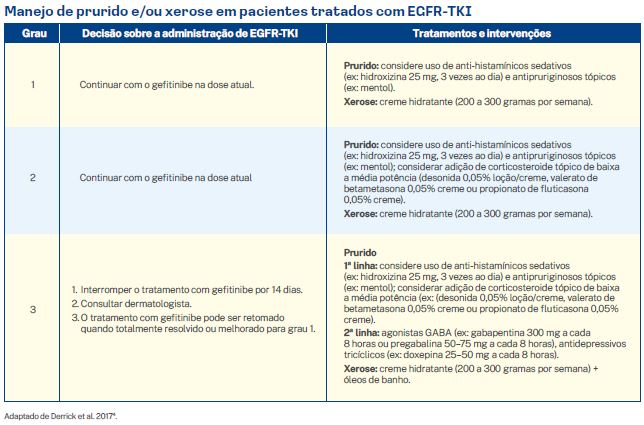

3.1.3. Prurido e xerose

Prurido

O prurido ocorre em quase metade dos pacientes tratados com EGFR-TKI e, embora raramente requeira redução de dose ou descontinuação da terapia medicamentosa, pode ter um impacto na qualidade de vida do paciente. É importante observar que a ocorrência de prurido geralmente acompanha erupção cutânea acneiforme no início; portanto, é importante enfatizar que o tratamento da erupção cutânea acneiforme subjacente também pode aliviar os sintomas pruriginosos.

Xerose

A diferenciação anormal de queratinócitos devido ao uso de EGFR-TKI leva à deterioração do estrato córneo e consequente diminuição da produção de loricrina, que é a principal proteína que mantém unida a estrutura da epiderme. Este processo resulta na formação de um tecido que não consegue preservar a umidade, resultando em xerose. À xerose normalmente tem um início mais tardio (cerca de 30 a GO dias) com o uso de EGFR-TKI e geralmente acompanha ou sucede a erupção cutânea acneiforme.